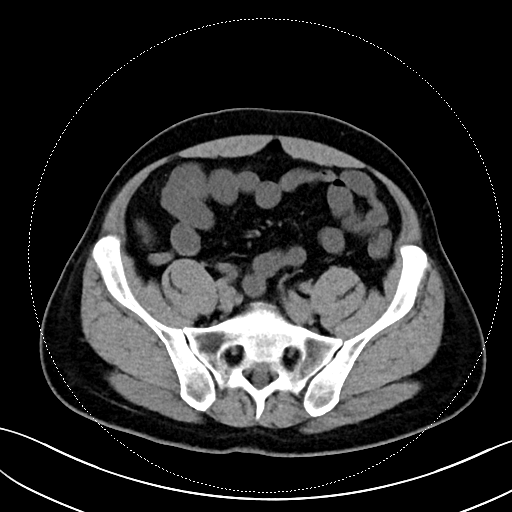

该患者的症状表现为钝痛,与进食、排便没有关联,也未出现发热、腹泻等伴随症状。在外院检查时,常规实验室检查如血常规、CRP、粪便钙卫蛋白均无异常,胃镜、结肠镜、胶囊内镜及超声内镜检查也未发现溃疡、肿瘤或克罗恩病的迹象。转诊至我院后,马师洋副教授团队另辟蹊径,对患者的腹部 CT 进行了细致入微的 「像素级」 阅片,并通过三维重建分析,敏锐地捕捉到阑尾根部呈现 「折角样」 扭曲,管腔局部狭窄且粘膜皱襞紊乱,虽无典型阑尾炎的周围脂肪条索、粪石等征象,但这一发现与患者的疼痛定位高度吻合,初步判断为非梗阻性阑尾功能障碍。